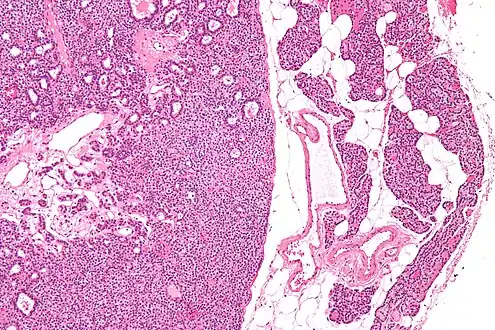

- Micrograph of a parathyroid adenoma (left) and normal parathyroid gland (right). H&E stain.

- Intermediate magnification